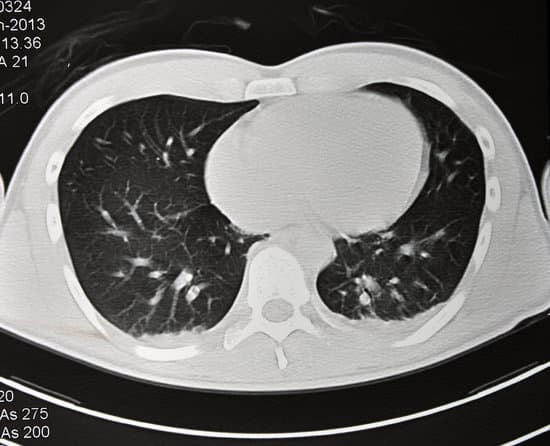

폐 CT 검사: 폐 질환의 조기 진단과 중요성

폐 CT(Computed Tomography) 검사는 폐와 기관지를 포함한 흉부 장기의 상태를 보다 정밀하게 확인할 수 있는 영상 촬영 기법입니다. X-ray 촬영보다 더 세밀한 영상을 제공하기 때문에 폐암, 폐렴, 폐섬유증, 결핵 등의 다양한 폐 질환을 진단하는 데 매우 효과적입니다. 특히 저선량 폐 CT는 폐암 조기 발견에 중요한 역할을 하며, 흡연자와 고위험군에게 권장되는 검사입니다.